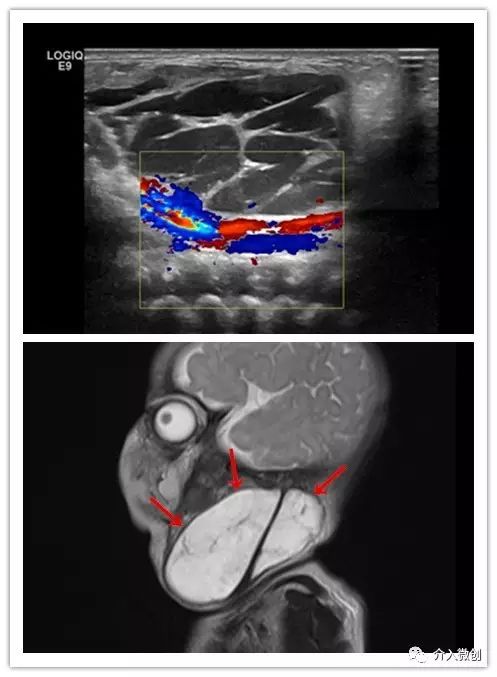

新生儿颈部巨囊型淋巴管畸形

颈部彩超及MRI检查提示颈部淋巴管畸形,瘤体内可见多发分隔囊腔。